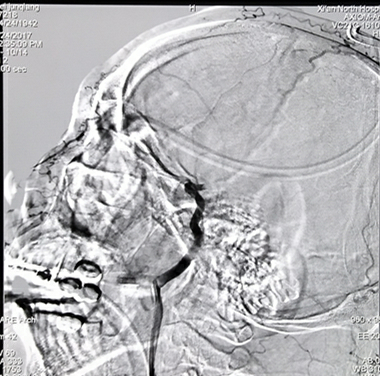

病例一:急性脑梗死取栓治疗

活动中突然跌倒昏迷。造影显示:右侧颈内动脉末端闭塞。(下图)